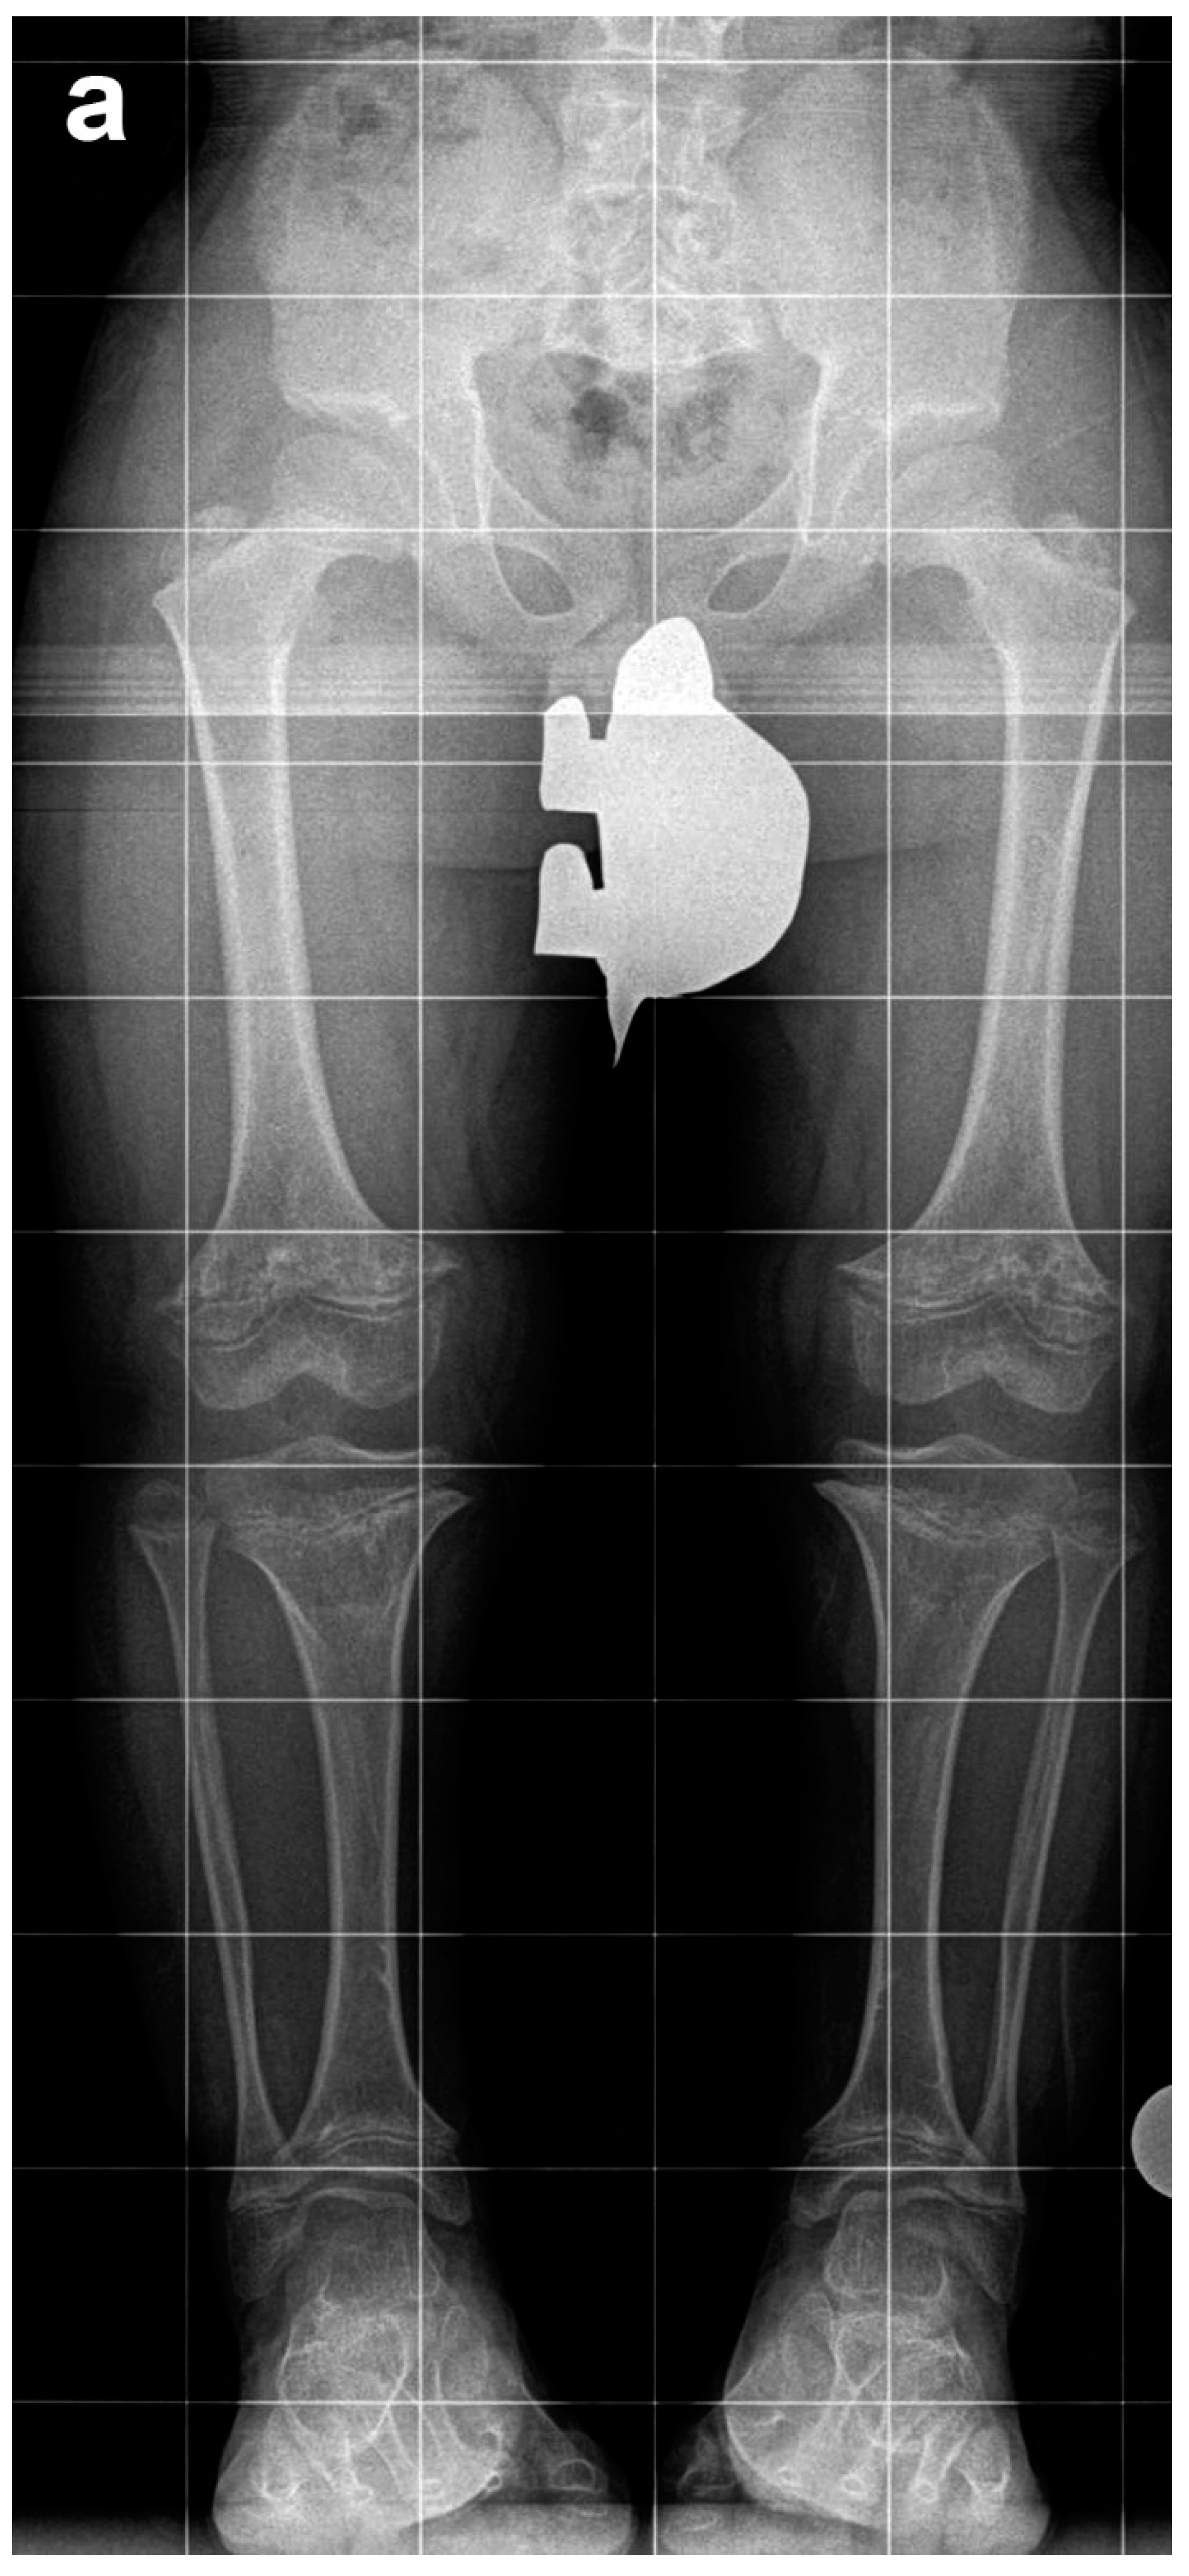

Figure 1. (a) Sequential extensive lengthening. (b) Moderate simultaneous bilateral femoral tibial lengthening (SBFTL). Both the extensive and the moderate strategies result in the same 20 cm of total lengthening (used with permission).

Limb lengthening with external fixators for achondroplasia has been reported by many groups [7,8,9,10,11]. Previous studies have reported bilateral extensive (~10 cm) femoral lengthening followed two years later by bilateral extensive (~10 cm) tibial lengthening. Such large individual lengthening can be very stressful on the limb (Figure 1a). A large (10 cm) lengthening of the tibia, for example, puts a large amount of stretching on the peroneal nerve. A previous article from this institute on double level tibia (10 cm) showed a very high peroneal nerve palsy rate [12].

In an effort to decrease the trauma to soft tissues and joints, we propose bilateral simultaneous moderate (5–7 cm) femoral lengthening and moderate (4–5 cm) tibial lengthening (Figure 1b). A few years after the initial lengthening, a second lengthening is performed. The specific length of time depends upon the desires of the family and child. The second lengthening consists of bilateral femoral lengthening (6–8 cm) and simultaneous bilateral tibial lengthening (4–6 cm). While extensive lengthening results in 20 cm of total lengthening, moderate lengthening may result in 21 to 25 cm of total lengthening (Figure 1b). We term this approach simultaneous bilateral femoral tibial lengthening (SBFTL).